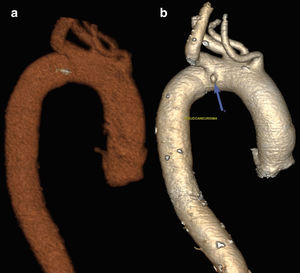

An 86-year-old woman with no medical history came to the emergency room due to dysphagia and shivering for 4 days after eating fish. Lab work-up: leukocytosis with left shift. Thoracic CT scan: esophageal circumferential thickening due to a foreign body associated with a small mediastinal hematoma, fatty reticulation and loss of fatty plane with the aortic arch (Fig. 1a); fishbone observed pointing towards the aortic arch (Fig. 2a). Diagnosis: esophageal perforation and suspected mediastinitis. Treatment: endoscopic extraction and conservative treatment. Follow-up CT scan: additional image in the aortic arch along the tract of the foreign body from previous CT scan (Fig. 1b). Diagnosis: aortic arch pseudoaneurysm (Fig. 2b). PET/CT scan: mediastinitis not ruled out. Treatment: antibiotic therapy for 2 weeks. Two-stage surgery: creation of space for non-fenestrated endovascular prosthesis, through right carotid subclavian transposition and aberrant right subclavian artery ligation; stent placement to exclude the pseudoaneurysm. No immediate postoperative complications were observed.